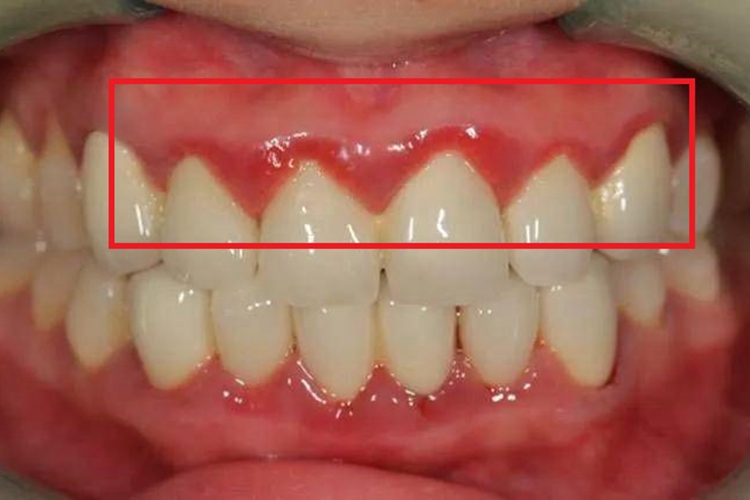

急性坏死性溃疡性龈炎可使局部出现大小不一的溃疡,表面红肿,并呈淡红色、鲜红色,形状并不规则,与周围的边界相对较清晰,可伴有疼痛、口臭等症状。